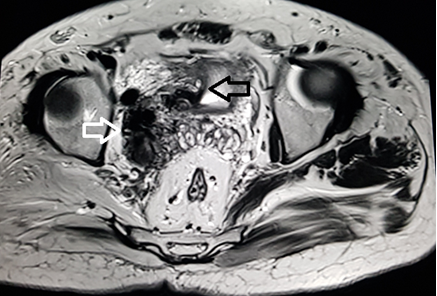

A 39 year old male presented with the chief complaint of pelvic discomfort and on and off haematuria. It was not associated with fever or urinary retention. No bowel symptoms were noted. Patient had history of paralytic poliomyelitis in his childhood and walked with crutches. On laboratory examination, patient was found to have deranged renal function tests with elevated creatinine level. Hence, we conducted MRI pelvis with MR urography to look for the urinary systemand to look for the status of the the pelvic muscles and joints. MR study showed multiple tortuous dilated vessels on the right side of pelvis suggestive of pelvic arteriovenous malformation (Figure 1&2). The arterial supply was noted from multiple branches of the right internal iliac artery and venous drainage was noted into right external iliac vein and deep external pudendal vein. The tangle of vessels was abutting the right lateral wall of urinary bladder, prostate and right seminal vesicle medially (Figure 1&3). It was abutting the obturatorinternus muscle laterally. There wasasymmetric thickening of the right lateral wall of urinary bladder adjacent to the vascular malformation (Figure 1). It was not associated with perivesicular fat strandings or enlarged locoregional lymphnodes. No restriction of diffusion was noted in DWI images. Prostate and bilateral bilateral seminal vesicles were normal in signal intensity and morphology. As a sequalae of childhood poliomyelitis, diffuse atrophy of pelvic muscles was noted that was more prominent on the right side (Figure 4&5). T1 and T2 high signal intensity suggestive of fatty replacement was noted in bilateral psoas and right obturaterinternus mucle. Fatty atrophy of bilateral hip and proximal thigh muscles were also seen (Figure 5). Abduction and external rotation was noted at bilateral hip joints (Figure 4). Histological examination of the bladder wall revealed polypoid bladder mucosa with chronic inflammation consistent with polypoid cystitis. Arteriovenous malformation was managed with intra-arterial coil embolization and subsequently the patient’s symptoms improved.

Figure 2 MRI coronal T2 weighted image through the pelvis demonstrate dilated tortuous vessels (white arrow) on the right side of pelvis abutting the right seminal vesicle (black arrow).